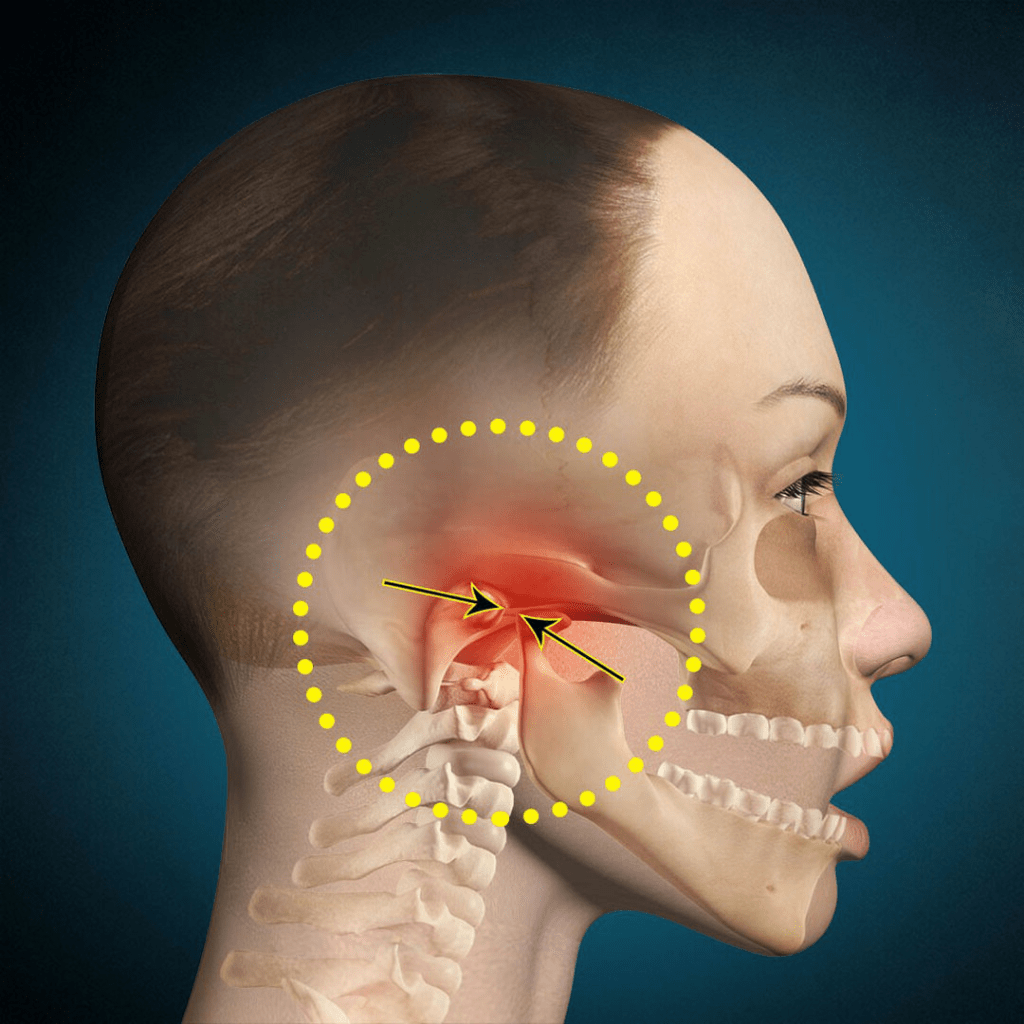

Disfunção Temporomandibular e Dor Orofacial (DTM e DOF)

Trata das disfunções musculares e articulares do sistema mastigatório, bem como das dores crônicas orofaciais de origem não odontogênica. Atua de maneira interdisciplinar, muitas vezes junto à fisioterapia e à neurologia.